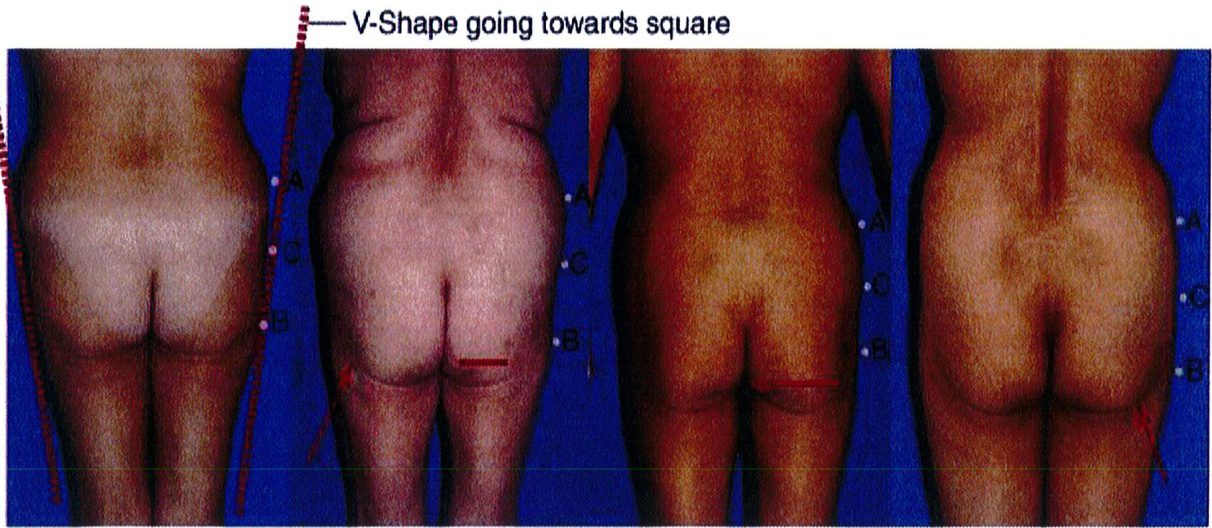

Khoảng 15% số bệnh nhân có dạng khung hình chữ V. Khi nối điểm A và B với nhau, có thể thấy chúng hội tụ lại 1 điểm ở dưới mông, tạo hình chữ V. Hầu hết mô mỡ nằm ở vùng mặt ngoài hông (điểm A) và rất ít ở điểm B. Ở dạng này, tình trạng lõm ở điểm C không quá đáng ngại. Khi điểm A nhỏ đi, mông sẽ có khung vuông.

Hình dạng này cũng có thể có dị tật liên quan tới lượng chất béo hoặc da dư thừa ở vùng dưới trong nếp lằn mông (vị trí nằm giữa đường liên mông và nếp lằn mông 2 bên). Vùng này quá đầy tạo ra hình ảnh trông như đang mặc tã lót, sẽ không đảm bảo tính thẩm mỹ.

CƠ MÔNG LỚN

Dạng khung mông hình chữ V là dạng khó chỉnh hình nhất. Hình dạng chữ V này không hấp dẫn người nhìn cho lắm, nên có thể cải thiện bằng cách hút mỡ ở điểm A và vùng mạn sườn. Đồng thời cũng cần ghép mô mỡ vào vùng mặt ngoài đùi trên để cải thiện hình dạng chữ V này (Hình 15) trong những trường hợp khó. Ngoài ra nếu điểm C có vùng lõm quá rõ ràng thì cũng nên ghép mô mỡ thêm vào để cải thiện tính thẩm mỹ của khu vực.

Hình. 15. Khung hình chữ V, cao với khối cơ mông lớn ngắn trước (trái) và sau (phải) phẫu thuật tạo hình.